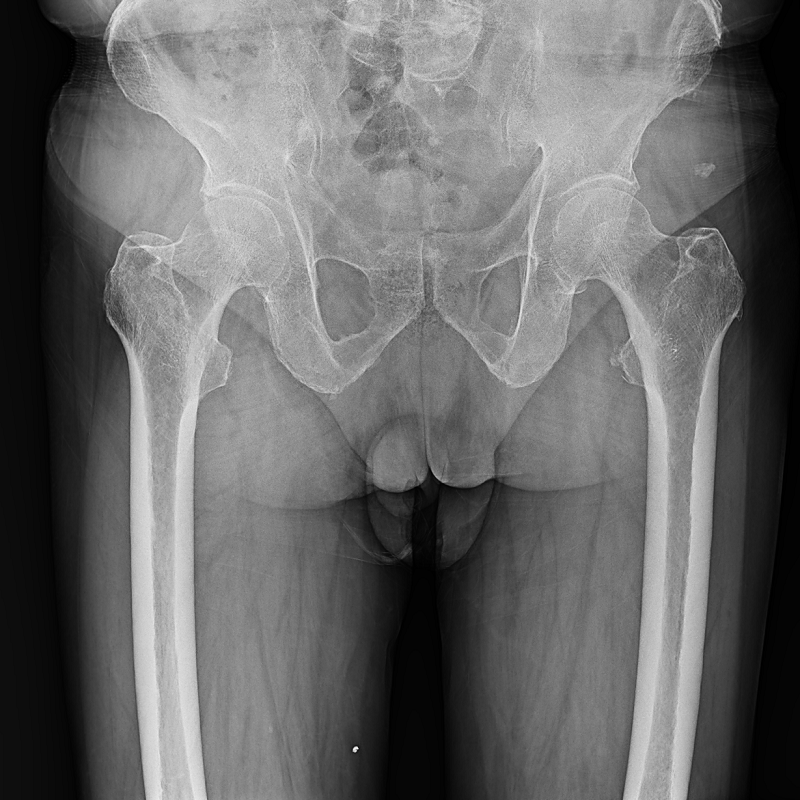

集靜態(tài)DR攝影與動(dòng)態(tài)的透視、造影功能于一身,可進(jìn)行頭部、胸部、腹部和四肢等部位的DR靜態(tài)攝影、各種動(dòng)態(tài)及造影檢查,還能在可視的情況下完成高清DR點(diǎn)片,有效避免傳統(tǒng)靜態(tài)DR盲拍造成的漏診和誤診,滿足多種臨床診斷需求。

搭載17x17英寸動(dòng)態(tài)平板探測(cè)器,動(dòng)態(tài)幀率高達(dá)30幀/秒,突破傳統(tǒng)盲拍局限,通過動(dòng)態(tài)實(shí)時(shí)連續(xù)成像,對(duì)于重疊部位、易被遮擋的病灶進(jìn)行多角度動(dòng)態(tài)觀察,瞬時(shí)實(shí)現(xiàn)高清點(diǎn)片,提升篩查診斷的精準(zhǔn)性。

● 圖像拼接

系統(tǒng)可以識(shí)別曝光圖像,無需設(shè)置識(shí)別點(diǎn)即完成精準(zhǔn)拼接,呈現(xiàn)大范圍完整影像。